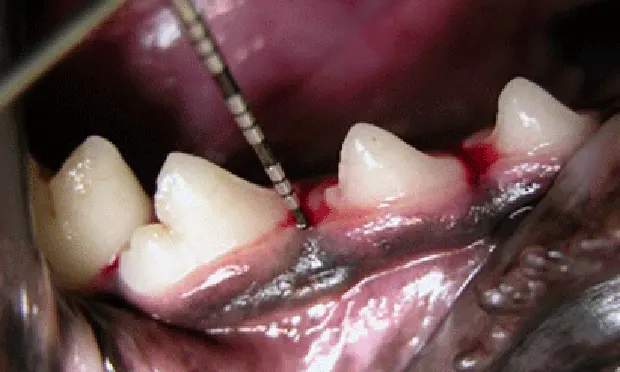

Dental probe being  inserted into sulcus of the right mandibular premolar tooth of a dog.